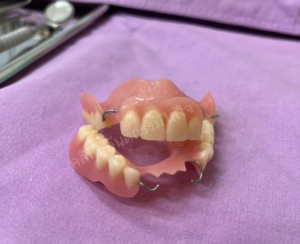

ฟันปลอมชนิดถอดได้

• ฟันปลอมฐานพลาสติก

• ฟันปลอมทั้งปาก

• ฟันปลอมฐานโลหะ